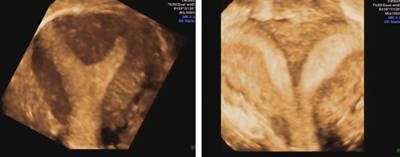

6. 三维超声检查:先用二维超声对子宫进行评估。推荐在月经中期或黄体期进行三维超声检查, 因在该期能最清晰的显示子宫内膜层及宫腔的形态。

(图:部分纵隔子宫(左)和完全纵隔子宫(右)的三维超声)